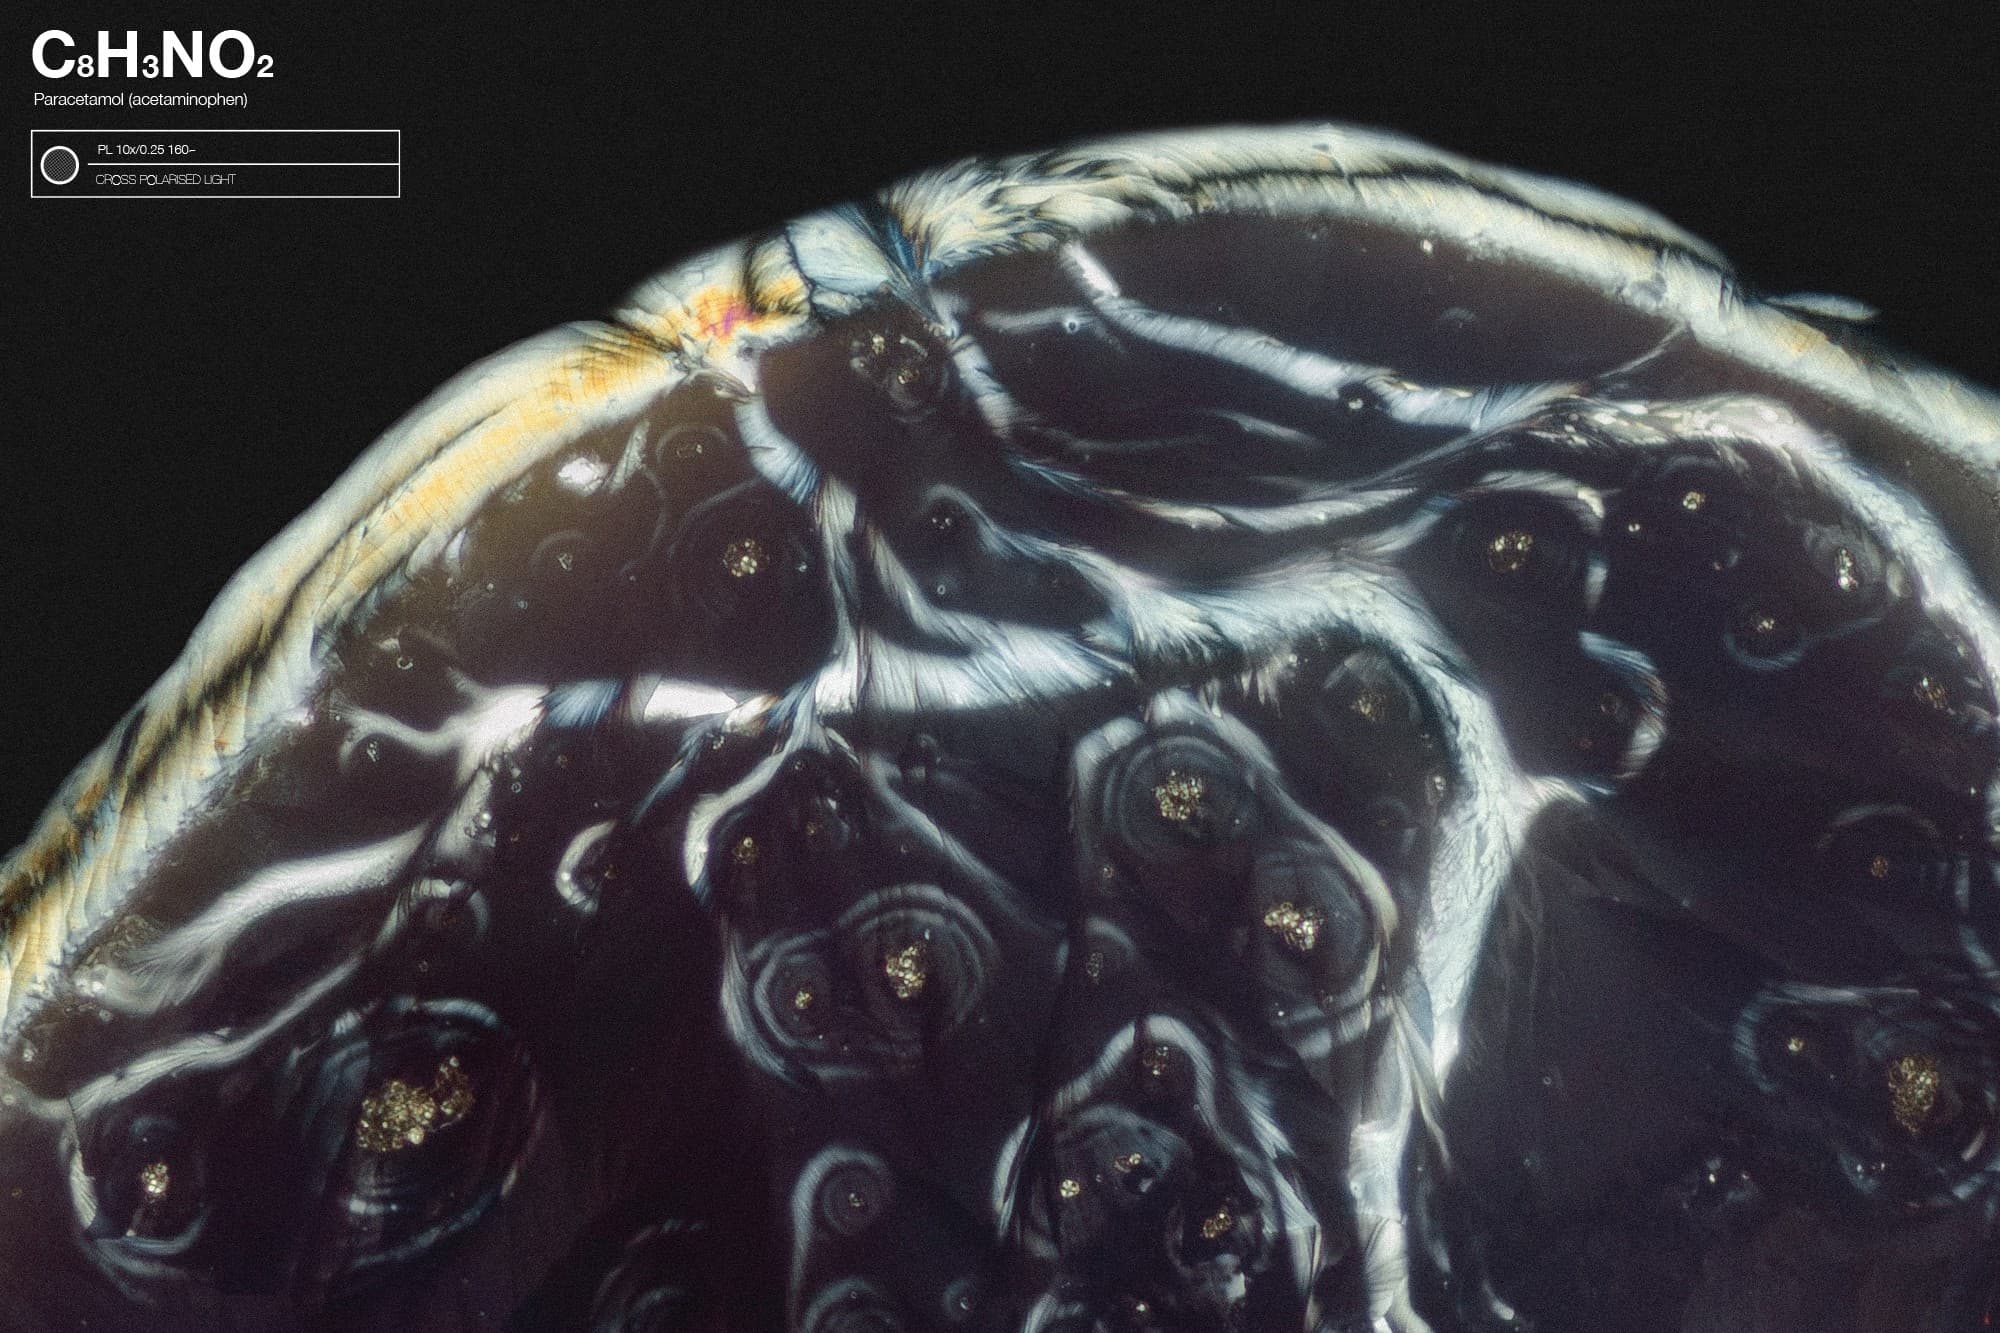

Have you ever wondered what your prescription — and illegal — drugs look like? Really look like — up close and personal?

Drawing on his background as a former intern doing toxicology and parasitology research at the Netherlands’ national public health department, Mikkers started photographing liquified samples of common, over-the-counter painkillers, such as acetaminophen, under his cross-polarized microscope (which allows him to bring in more light through the sample). The results were visually stunning, revealing psychedelic patterns that look like oil slick-like waves or marbles.

To prepare a drug sample like the one above, Mikkers begins by smashing a pill into a powder and then liquefying it by mixing in de-mineralized water or alcohol. “With that liquid, I can make a little drop” about 1–5 millimeters wide on a microscope slide, he says, which he lets dry at room temperature. Sometimes the concoction crystallizes in seconds; sometimes Mikkers has to put the slide in storage for weeks or months before seeing any notable differences. “I never know what’s going to happen.”